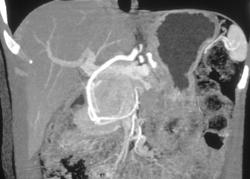

Cystadenoma Pancreas and Renal Cancer - Von Hippel-Lindau syndrome (VHL)